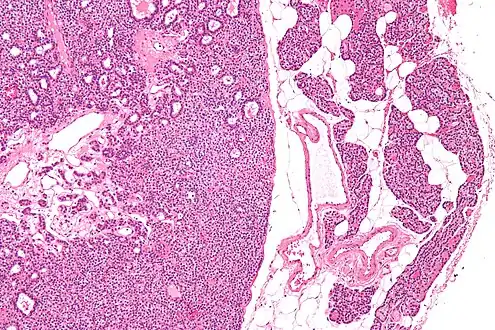

Micrograph of a parathyroid adenoma (left) and normal parathyroid gland (right). H&E stain.

Normal parathyroid gland with prominent adipose tissue is seen on the right of the image.-High magnification

Intermediate magnification